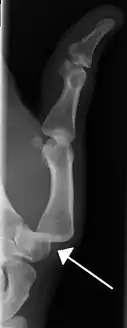

Radiograph of right fifth phalanx bone dislocation